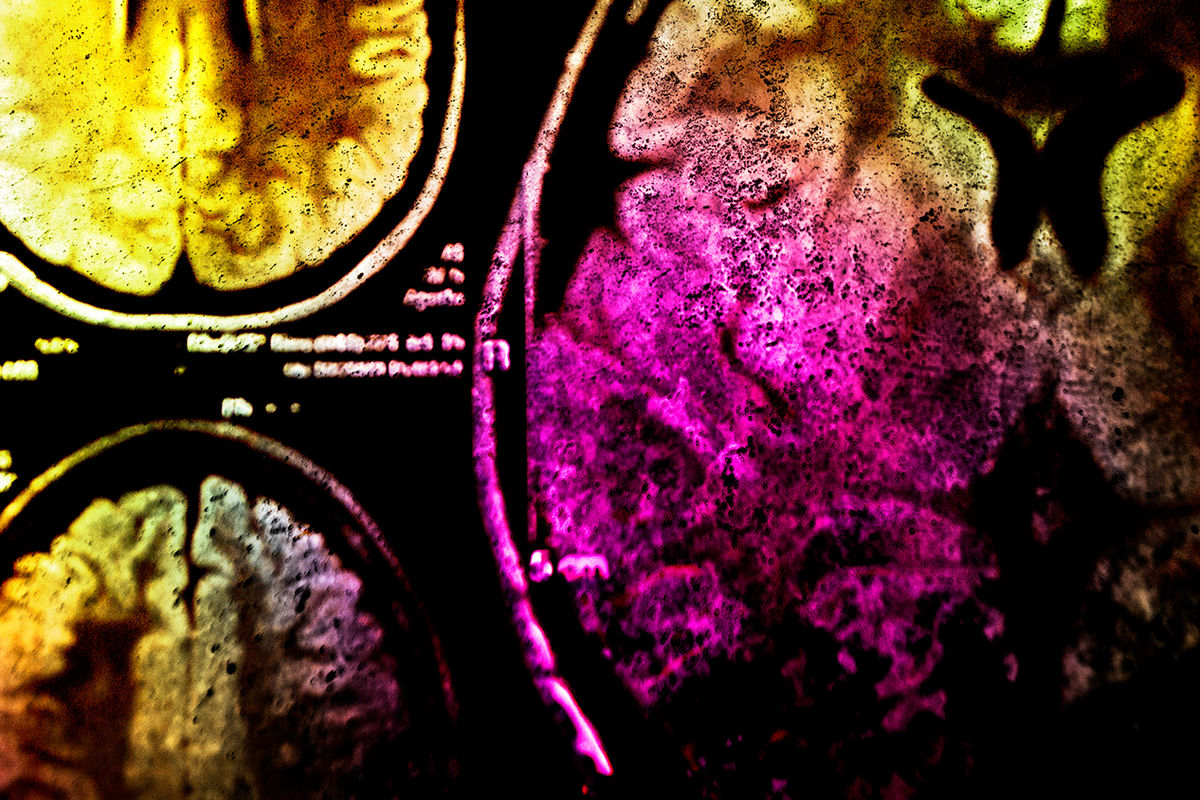

Марреро и его коллеги рассматривали истории болезни пациентов, изучали состояние мозга больных с помощью МРТ, делали токсикологические пробы, наблюдали за метаболизмом, брали анализ спинномозговой жидкости, исключали возможные диагнозы один за другим — слабоумие, нейродегенеративные и аутоиммунные заболевания, инфекционные болезни — ничто из этого не подходило.